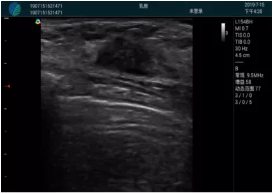

腺體內(nèi)部清晰顯示一低回聲塊影,形態(tài)不規(guī)則,邊界模糊,邊緣呈毛刺狀,內(nèi)部見砂礫樣鈣化

M20引導(dǎo)下穿刺活檢術(shù)